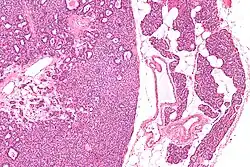

Micrograph of a parathyroid adenoma (left) and normal parathyroid gland (right). H&E stain.

Hyperparathyroidism is confirmed by blood tests such as calcium and PTH levels. A specific test for parathyroid adenoma is sestamibi parathyroid scintigraphy, often referred to as sestamibi scan or, more colloquially, MIBI scan. This nuclear imaging technique reveals the presence and location of pathological parathyroid tissue.[7] In cases where 99mTc-sestamibi scintigraphy or SPECT delivers inconclusive results, other imaging modalities and tracers can be applied. For detection of multiple parathyroid adenomas, positron emission tomography (PET) using the radiopharmaceutical 68Ga-Trivehexin[8] has demonstrated a higher detection rate (94.1%) than 99mTc-sestamibi imaging (58.8%).[9]